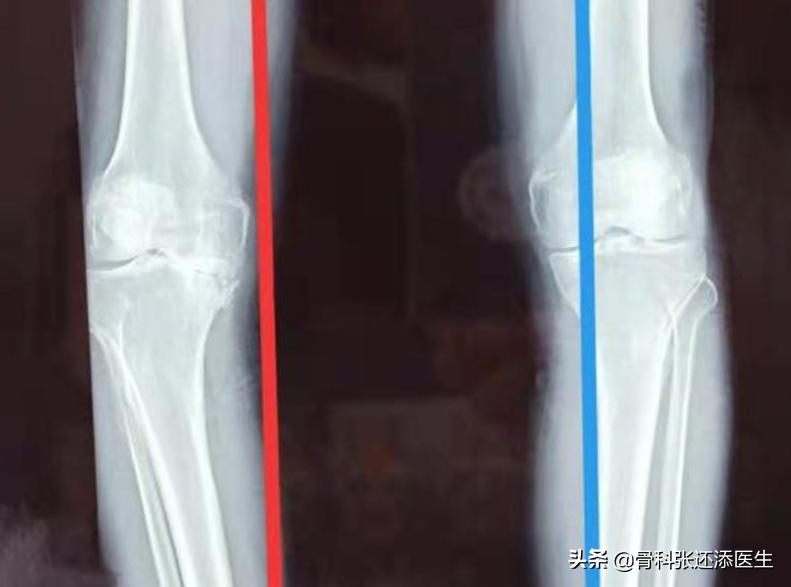

x光表现:严重的关节间隙狭窄,大量的骨赘,明显的软骨下骨硬化,明显的膝关节骨性畸形。

左边(红色侧)严重的关节间隙狭窄

当然,也会有朋友出现疼痛值比较高但影像学表现不明显,或是不疼但影像学表现骨关节炎相对严重的情况,这种分期就比较复杂,在指南中也描述的比较专业。大家就不必太纠结,医生会有明确的判断的。